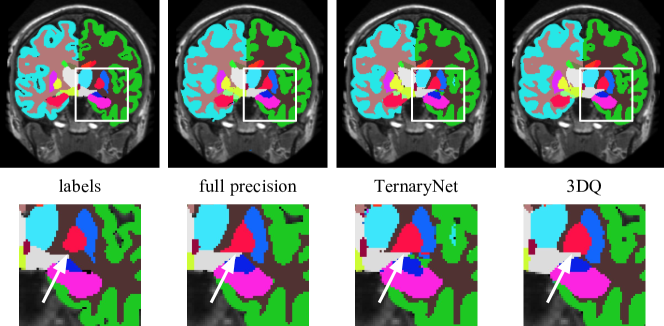

Refer to caption

Figure 3: Qualitative results of 3DQ compared with baseline methods. White arrows on the zoomed views show the superior segmentation performance of 3DQ.

Figure 3 shows sample segmentations for a slice of a MALC volume from 3D U-Net. A zoomed view of the segmentations, indicates important subcortical structures with a white arrow. Both full precision and TernaryNet predictions suffer from over-inclusion of small structures and spurious misclassified regions. The box plot in Figure 4 confirms the higher quality of the segmentations produced by 3DQ, reporting the Dice scores on the right hemisphere structures. 3DQ outperformed both full precision and TernaryNet, with fewer outliers, demonstrating more uniform results throughout the samples.